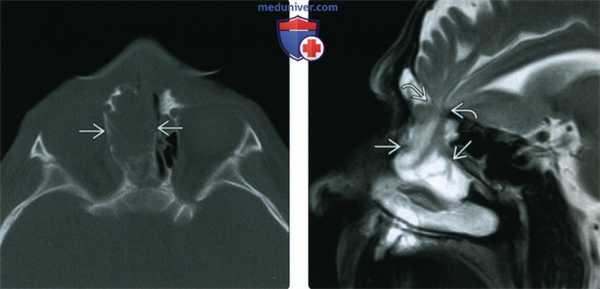

(Слева) Бесконтрастная КТ, аксиальный срез: у мальчика с объемным образованием глабеллярной области (лобно-носовое цефалоцеле) определяется отсутствие носовых костей и носовых отростков лобной кости, а также объемное образование ликворной интенсивности сигнала в глабеллярной области. Отмечается легкий гипертелоризм. Височный рог левого бокового желудочка расширен.

(Справа) МРТ, Т2-ВИ, сагиттальный срез: у этого же пациента определяется дефект кости рядом с лобно-носовым швом, содержащий объемное образование ликворной интенсивности сигнала. Такая картина согласуется с цефалоцеле. Наблюдается дисморфизм мозолистого тела.